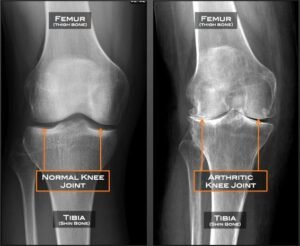

Comparison X-rays showing a healthy knee joint and a knee affected by osteoarthritis

Knee osteoarthritis is a degenerative joint condition where the cartilage that cushions the knee gradually wears down. This can lead to:

Osteoarthritis can affect one or both knees and may progress at different rates depending on activity levels, body weight, previous injuries and genetics.